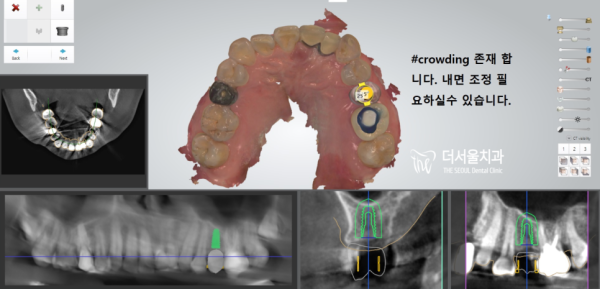

정확한 임플란트 식립을 위해 구강스캔을 하고

내비게이션 임플란트 방식으로 임플란트 수술 계획을 세웁니다.

네비게이션 임플란트로 분석을 통해

완자분의 임플란트 식립계획을 세웠습니다.

정확하게 오차없이 계산된 그대로 임플란트를 심기로 했습니다.

디지털치과 태평역 더서울치과의 임플란트는

이렇게 오차없이 정확한 임플란트를 심어드립니다!